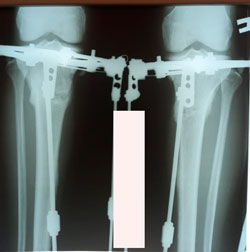

Исходник 40 лет.

Дата операции - 18.09.2020